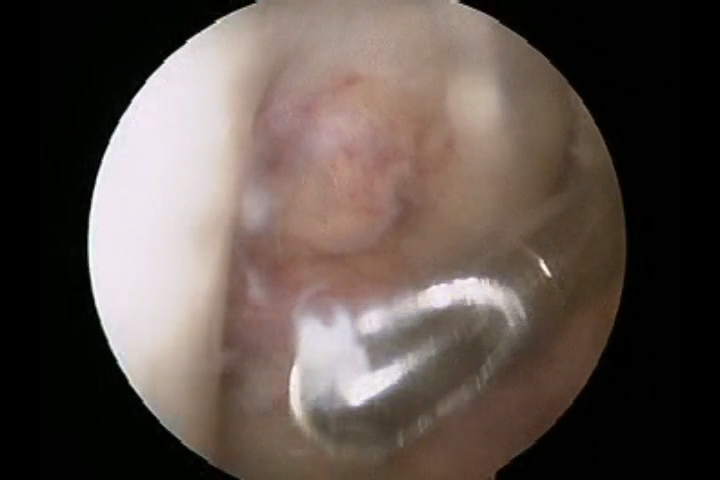

There used to be a common consensus that ACL reconstruction of knee should not be done in old age, this idea has now largely been debunked with statistical evidence. this 68 year old man with a traumatic anterior cruciate ligament tear had intact lateral and medial meniscus and quite normal cartilage in the weight bearing areas of knee, under such circumstances arthroscopic ACL repair should be done for a better outcome for the knee